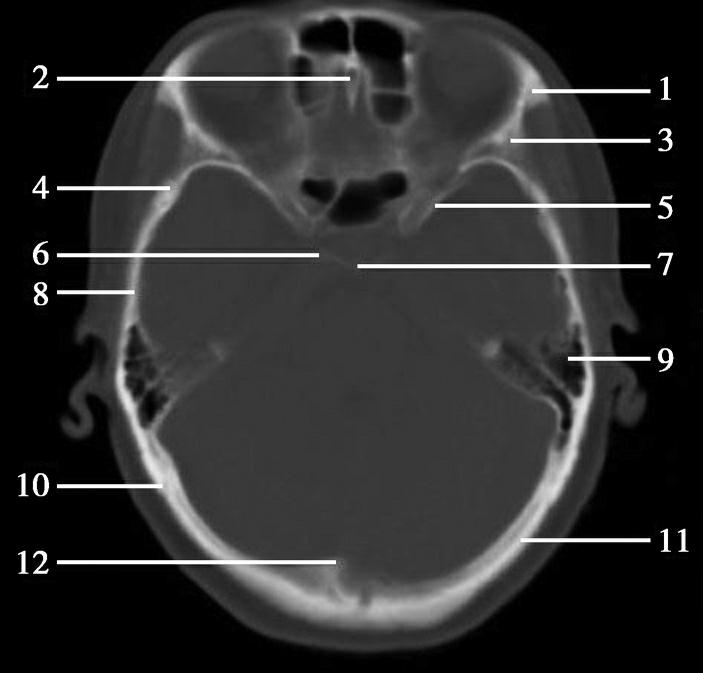

颅底分前、中、后颅窝,借孔道与颅外相通。前颅窝底筛孔内穿行嗅神经。中颅窝底视神经管,内有视神经及眼动脉走行;眶上裂走行眼静脉、动眼神经、滑车神经、外展神经、三叉神经眼支;圆孔内穿行三叉神经的上颌支,卵圆孔穿行三叉神经下颌支;棘孔内可有脑膜中动脉及静脉走行,三叉神经下颌支的脑膜支亦经棘孔进入中颅窝;颈内动脉经破裂孔进入颅内,颈上神经节发出交感神经丛的颈内动脉神经穿破裂孔在海绵窦内形成海绵丛。后颅窝内枕骨大孔内可有延髓、椎动脉穿行,副神经脊髓根经枕大孔入颅与副神经颅根汇合;颈静脉孔内穿行颈内静脉、迷走神经、副神经及舌咽神经;内耳道穿行面神经及前庭蜗神经、迷路动静脉;舌下神经管穿行舌下神经(图1-2-85)。

图1-2-85 颅底孔道CT解剖

1.筛孔;2.视神经管;3.破裂孔;4.内耳道;5.颈静脉孔;6.眶上裂;7.圆孔;8.卵圆孔;9.棘孔;10.舌下神经管;11.枕骨大孔